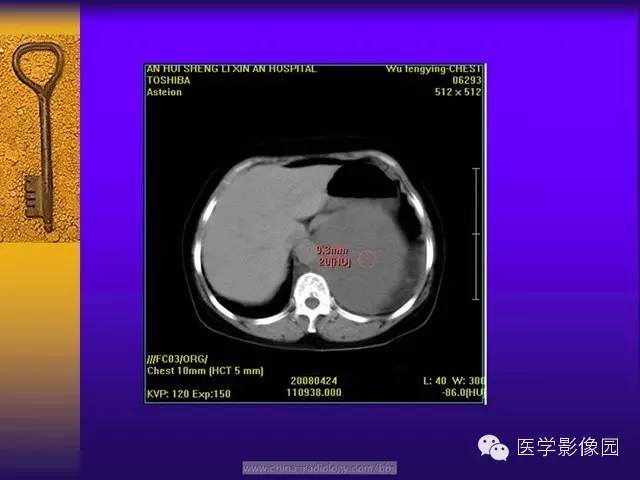

CT 平扫肿瘤密度以不均匀居多,肿瘤体积较小时密度可较均匀,随着肿瘤体积的增大其内部或周边可出现大小不等的低密度区,肿瘤越大坏死囊变的区域越大,形态越不规则。这与肿瘤细胞、胶原纤维的分布及二者发生玻璃样变、黏液样变及坏死囊变有关。肿瘤的供血血管由边缘向肿瘤内部延伸,肿瘤中心易出现血供不足而出现坏死、囊变。肿瘤越大坏死囊变的区域越大,形态越不规则。